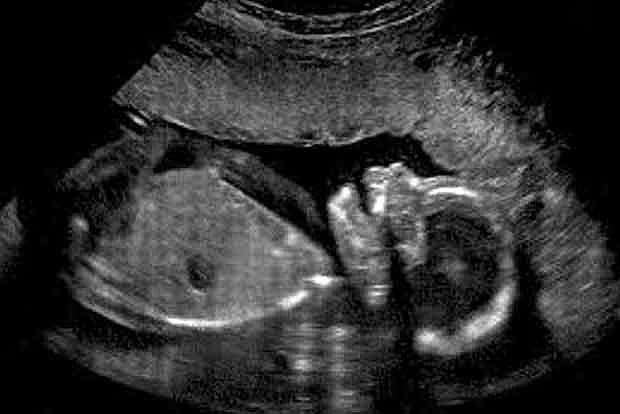

A retired government doctor, who was running a private hospital at Kalayarkovil in Sivaganga district, was booked after he was found to have revealed the sex of the foetus on Thursday.

Arun Dhandapani retired from the Sivaganga Medical College Hospital. Later, he started a private hospital with an attached scan centre. There were complaints that he had been revealing the sex of the foetus to the parents and had been making money.

As the practice of revealing the sex of the foetus is a crime under Pre-natal Diagnostic Techniques (Regulation and Prevention of Misuse) Act of 1994, there were several complaints lodged with the District Health Department about him.

An expert committee of three members in the rank of Joint Directors were formed and the team comprising  Sivaganga JD Vijayan Madhamadakki, Madurai JD Rukmani, Chennai JD Gurunathan inspected the hospital on Thursday. They found the complaints to be true and the team also noticed that the person operating the scan centre was not trained. They sealed both the scan centre and the hospital.